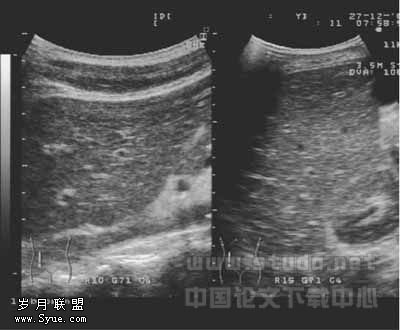

271例Ⅱ、Ⅲ级肝内胆管较均匀或节段性扩张,内径一般<3mm;Ⅱ、Ⅲ级及部分Ⅰ级胆管壁呈节段或弥漫不均匀增强、增厚,见图1,部分管壁出现不规则钙化斑,可伴有声影,胆管壁与门静脉分界不清,周围肝组织回声增强、增粗。其中4例合并被膜下小胆管囊状扩张,均<2cm,见图2。华支睾吸虫病在肝内的分布无明显特异性,但随着年龄的增长,其超声表现有由肝内胆管的扩张到胆管壁增厚、钙化、回声增强,周围肝实质回声增强、增粗这样一个趋势。

图1 肝内胆管节段性扩张,管壁增厚、回声增强、钙化